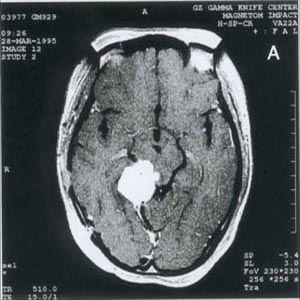

脑肿瘤mri波谱图片(脑肿瘤ct图片)

脑肿瘤CT图片